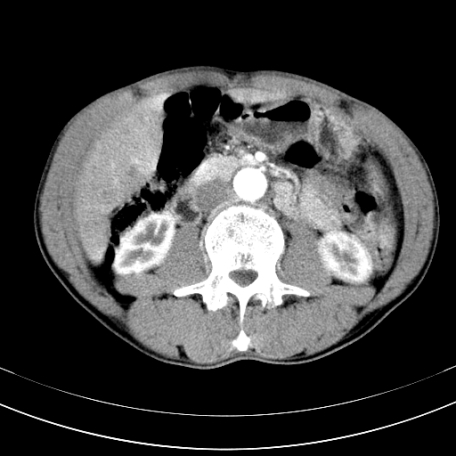

标题: CT21441:男55岁,上腹部胀痛半年余,请老师们看看是后腹膜淋巴 [打印本页]

标题: CT21441:男55岁,上腹部胀痛半年余,请老师们看看是后腹膜淋巴

腹主动脉右侧有一个,有肿瘤病史吗?

转移瘤或淋巴瘤

腹膜后淋巴结肿大,原因待查。